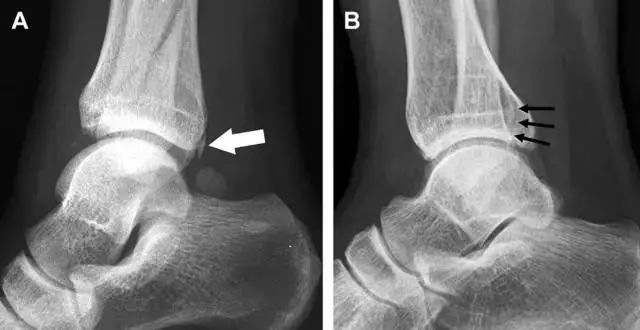

16

胫骨后踝骨折

涉及到三角韧带和外侧副韧带(LCL)的复杂性骨折常常不难发现,尤其是存在表面软组织肿胀时。然而,后胫腓韧带牵拉引起的胫骨后踝骨折则很难发现。这些骨折大小不一(图 2),却很重要,因为他们常与胫骨远端螺旋骨折有关,或者是三踝骨折的一部分。

图 2 胫骨后踝骨折。A 侧位片示来源于胫骨后踝的一个小骨折碎片(箭头),因踝部扭伤导致;B 另一位跖屈损伤的患者,侧位片示一个大骨折块(箭头)。